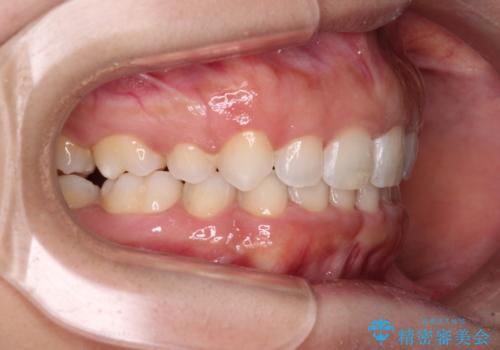

上下顎ともに前突しており、特に上顎は著しい突出感でした。

また、下顎歯列には左右差があり、非対称な抜歯が必要と判断されたため、治療は困難なものとなりました。

それでも根気強く通院してくださり、横からの顔貌の印象が大きく改善され、スムーズに口が閉じられるようになりました。